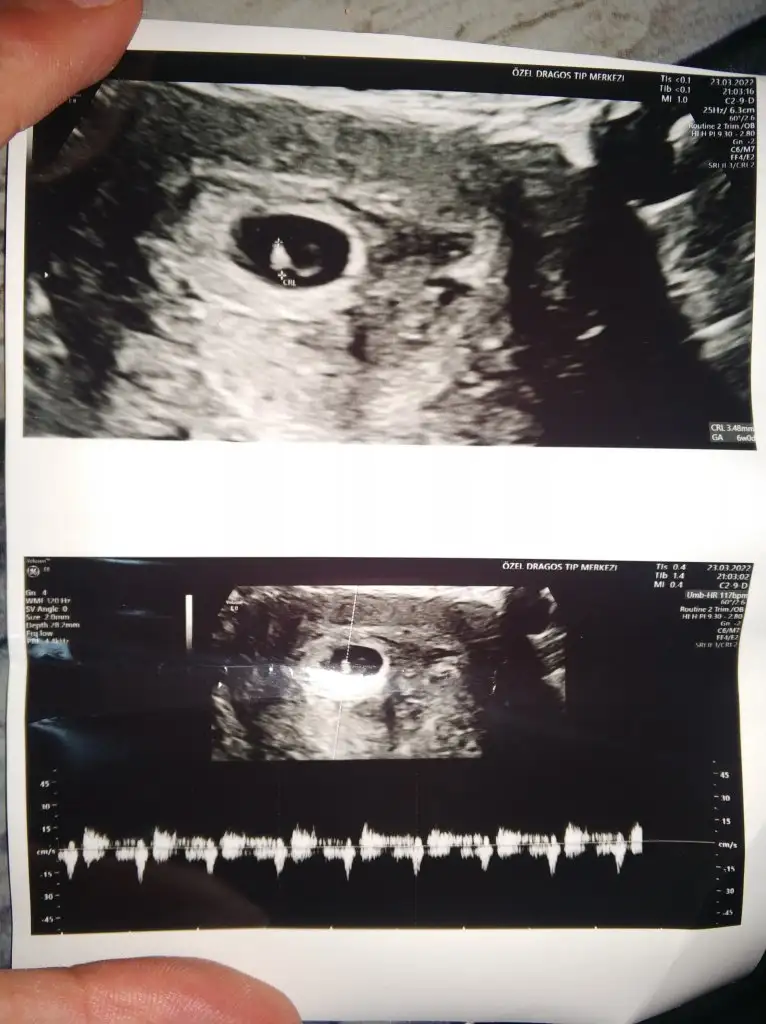

kuzum bu tosunpaşaya benziyorCanım ben de bir cinsiyet tahmini alabilir miyim ? Karından bakıldı ve 6 haftalık suan. Eki Görüntüle 3033530

kuzum bu prenses gibi

Hadi bakalım canim gönül prensesten yana ama önemli olan sağlıklı olması tabiikuzum bu tosunpaşaya benziyor